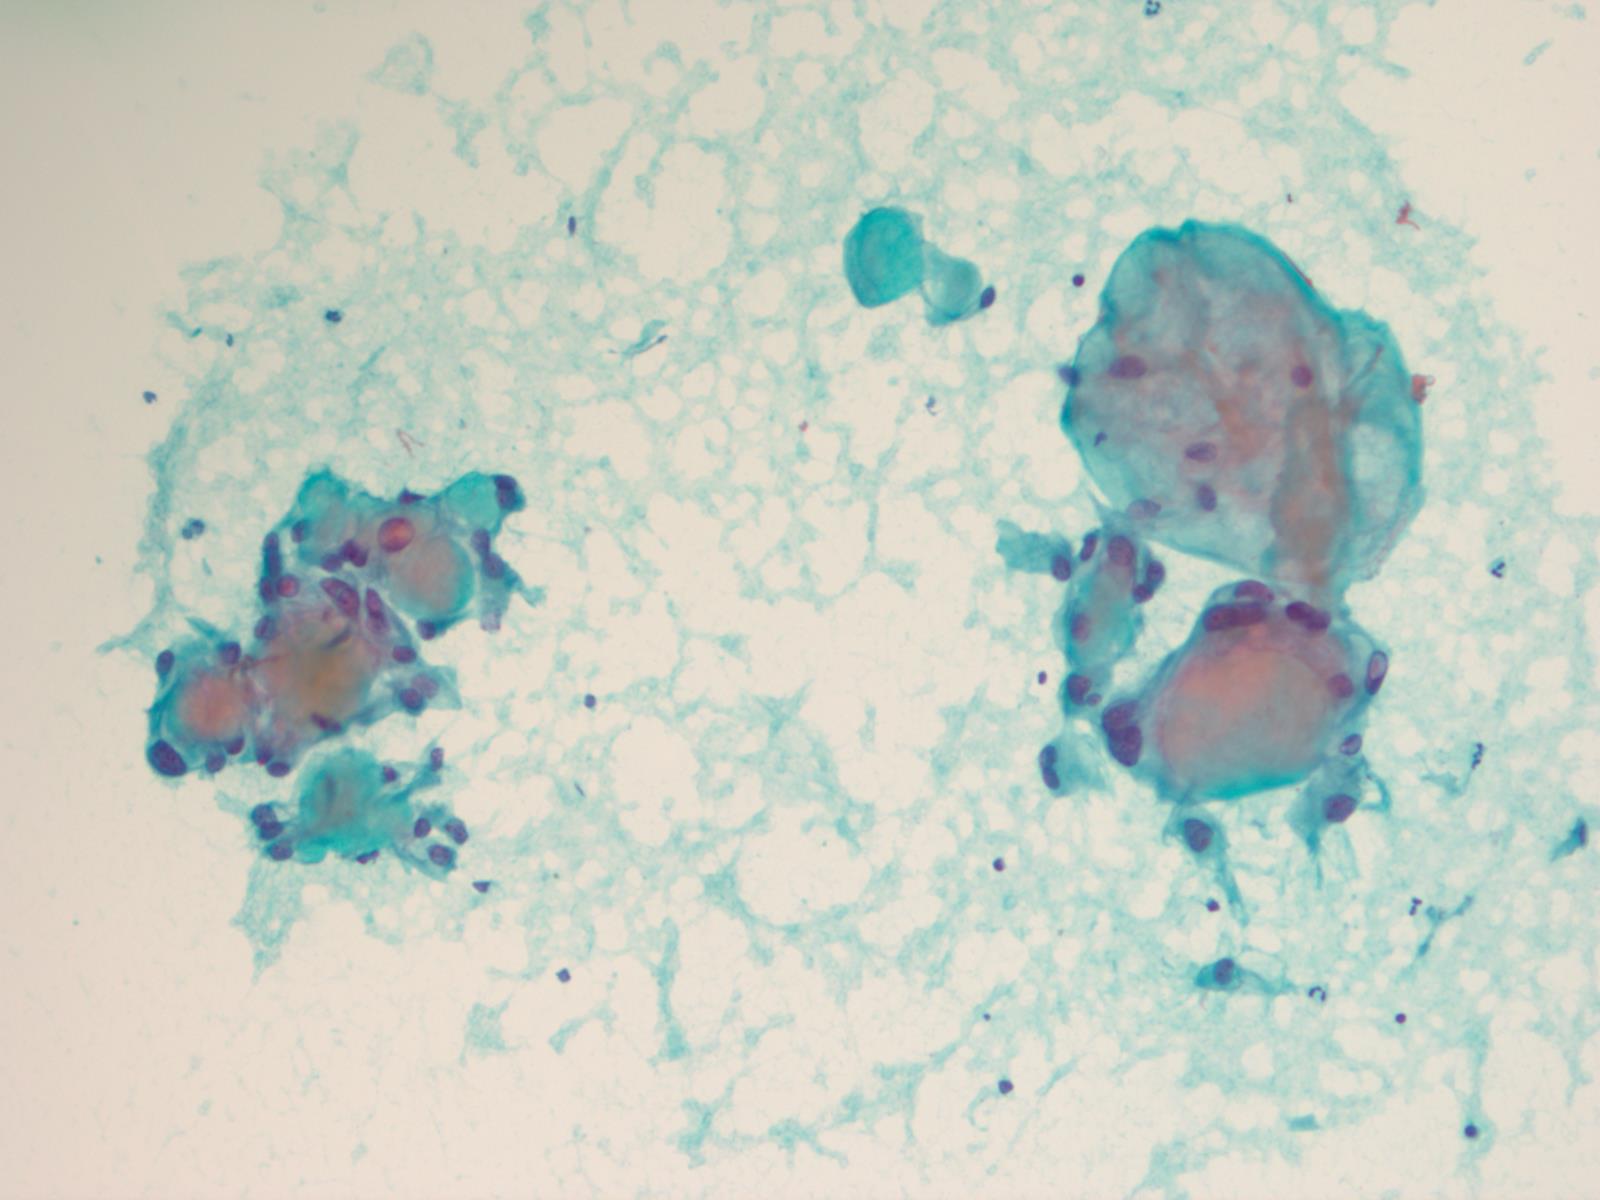

Frozen section description

- Intraoperative squash / smear preparation and frozen section reveals epithelioid to spindled tumor cells arranged around microcysts and forming papillary structures with perivascular myxoid change; these features are diagnostic in the appropriate clinical setting

Cytology description

- Cytology usually recapitulates the histologic findings; myxoid matrix and cells show nuclear uniformity and process formation

- Epithelioid to spindle cells

- Arrangement of tumor cells around blood vessels forms papillary structures with perivascular myxoid change

- Tumor cells are arranged around myxoid microcysts

Cytology images